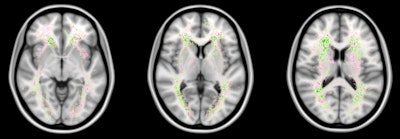

False negatives are the most common source of error for both humans and computers. The images show a spatial distribution of the false-negative white-matter hyperintensity segmentations of a human observer and the top 4 ranking methods in the WMH Segmentation Challenge. The colors indicate the differences. Green means that the top 4 methods had fewer false negatives, while pink means that the human observer had fewer false negatives. Overall, the top 4 AI methods had fewer false negatives than a human observer, but the AI methods made more mistakes at locations where lesions are rarely found. Images courtesy of Hugo Kuijf, PhD.